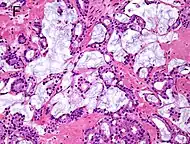

| Mucinous adenocarcinoma | 0.2%[12] | ![]() |

|

Tumorous glands: | 4+4=8 for irregular cribriform glands floating in mucin.[1] | ||